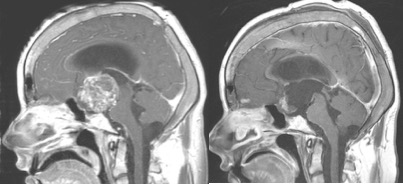

astrocytome pilocytique chiasma-ventriculaire (à gauche), patient valvé, obstructions de valve à répétition ; décision de débulking tumoral permettant de résoudre l’hydrocéphalie (à droite)